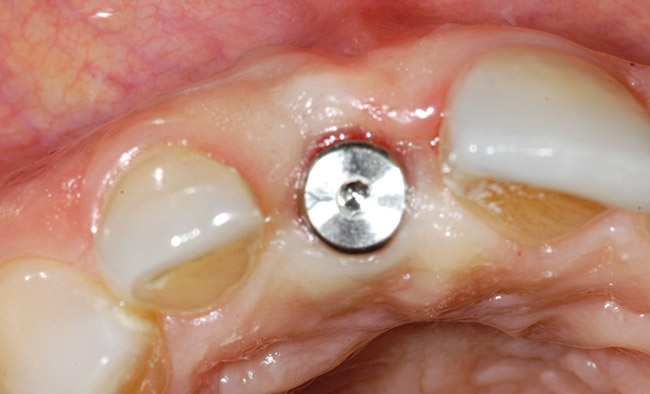

Treatment consisted of flapless extraction, socket grafting using mineralized bone allograft (Puros®, Zimmer Dental Inc, Carlsbad, CA), and a pedicled connective tissue graft36,37(Figure 11). Five months post-surgery, reentry was accomplished via a mid-crestal and labial sulcular incision. A crestal plasty was per- formed before implant placement into type II bone (Figure 12 and Figure 13). An immediate provisional was used for 3 months (Figure 14) before final crown fabrication (Figure 15).

Figure 12  Stage I surgery (implant shown with healing abutment), 4 months after extraction and socket graft.

Figure 12

Figure 13  Primary flap closure.